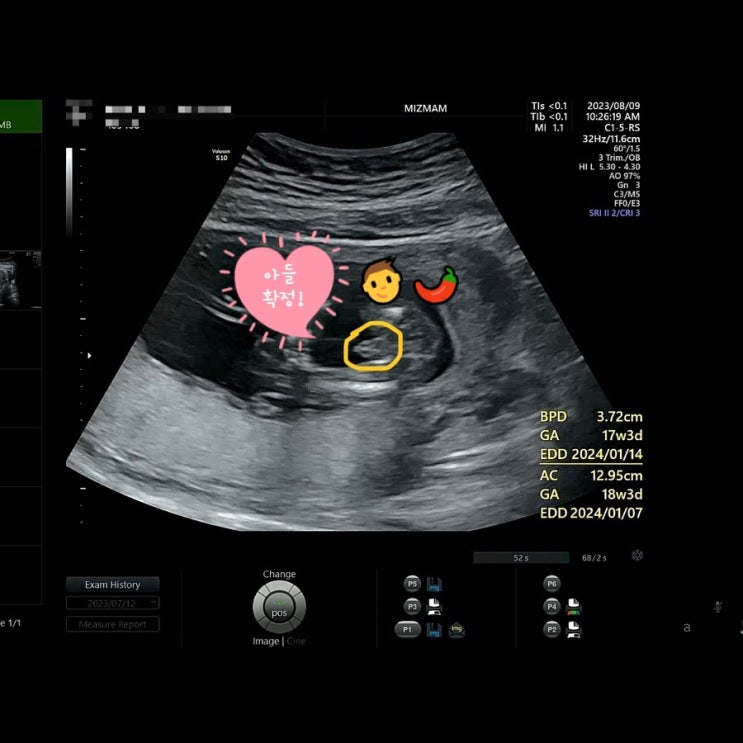

[임신일기/쑥쑥이 성장기록] 임신 17주차 초음파, 성별확인, 2차 기형아 검사결과, 태아성장보고서 쑥쑥 크고 있는 울 쑥쑤기

2023. 08. 09 (수) 당진 미즈맘으로 전원 후 딱 17주가 되는 날인 8월 9일! 2차 기형아 검사를 위해서 방문...